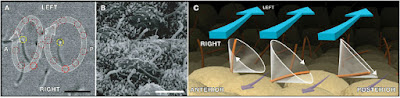

The upper image shows the PNEC’s in your respiratory tract (NE). They can be alone or be grouped into neuro- endocrine bodies (NEBs). A 2008 study, and several before it, has correlated a hyperplasia and hypertrophy of PNECs with Sudden Infant Death Syndrome. Too many and your respiratory control may get thrown out of whack; it may just stop working. It might be good to monitor the PNEC system in youngsters to try and predict susceptibility to SIDS. |

For one example, there are pulmonary neuroendocrine cells (PNEC) in every part of your respiratory tract, from your nose to your alveoli. While they seem to act like neurons in many respects, they are derived from epithelial tissue, not the neural crest tissue that all neurons come from.

Each PNEC spans the distance from basement membrane to the air conducting space. On the luminal side, they have microvilli that stick out into the lumen and sample the air as it passes. On the basal side (bottom) they communicate with neurons. Just what are they doing there?

They have several functions, including regulating the development of the respiratory system in the fetus. They also regulate the function of the respiratory cells by sensing oxygen levels, controlling the muscular tone of the bronchi, regulating pulmonary blood flow and modulating immune responses. The origin and function of PNEC’s is reviewed in a 2012 paper, which also highlights a problem with them – when PNEC’s go bad, they cause a deadly small cell cancer.

In response to what the cell senses, it will release a variety of chemicals, many of which can act as neurotransmitters – hence the reason they are considered neuroendocrine cells. But the PNEC’s may have another function, one hinted at in a 2014 study. The results of these experiments indicated that PNEC’s can detect chemicals in the air as it passes over their microvilli – they quite literally can smell the air, as their microvilli were found to have olfactory (smell) receptors, just like in your nose!